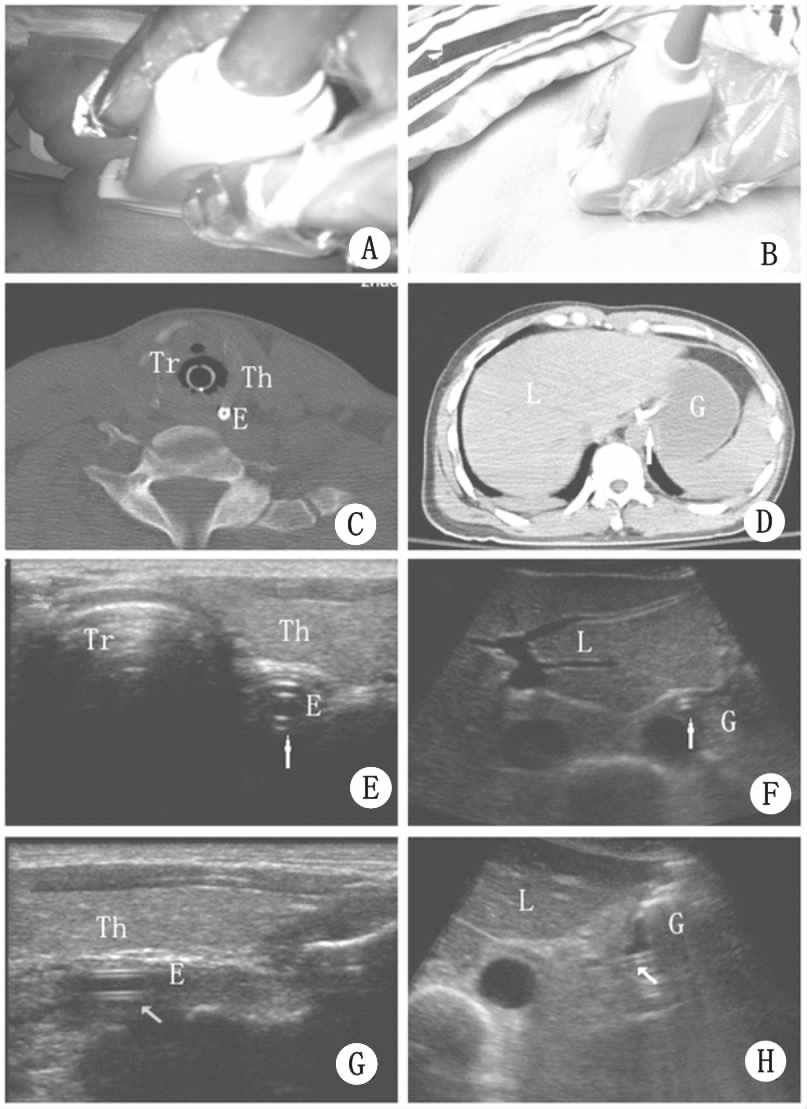

A:颈部超声扫查时探头的位置;B:腹部超声扫查时探头的体表位置;C:颈部的CT截面图,可见食道位于甲状腺左叶后内侧、气管左后方,食道内高密度亮点为鼻饲管;D:上腹部CT的截面图,贲门位于肝左叶后方、腹主动脉前方,贲门内高密度亮点为鼻饲管;E、G:颈部食道内的超声横截面和纵切图;F、H:胃贲门/胃体内鼻饲管超声图,受胃内气体干扰的鼻饲管只能部分显像。(Tr 气管;Th 甲状腺;E 食道;L 肝;G 胃) 图 1超声确定鼻饲管位置的方法

颈部超声定位法(超声法A)耗时(1.7±1.1)min,食道—贲门定位法(超声法B)耗时(6.4±2.4)min,胃体定位法(超声法C)耗时(10.3±4.5)min,X线检查法耗时(118.7±21.2)min。115例患者经X线检查共发现鼻饲管异位7例,其中气管内异位3例、食道内返折4例,总异位率6%,气管内异位率2.6%,2例典型的鼻饲管异位X线图像见图 3。3例鼻饲管气管内异位,在B超检查时均显示阴性结果,也即超声检查颈部食道、食道—贲门、胃体部均未探及鼻饲管,与X线检查结果一致;其中有2例抽吸液法,1例听诊法的结果阳性。4例食道内返折,超声在颈部食道探及鼻饲管,但在食道—贲门、胃体部均未探及;4例均未获得抽吸液,但均可闻及气过水声。

A:右下支气管内见鼻饲管影像,B:鼻饲管食道内折返 图 3鼻饲管异位的X线表现